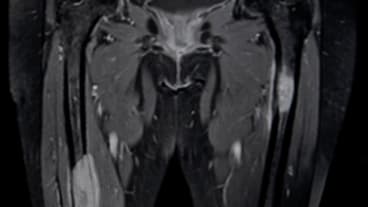

une IRM pelvienne ou une uro-IRM si l'uroscanner est contrindiqué;